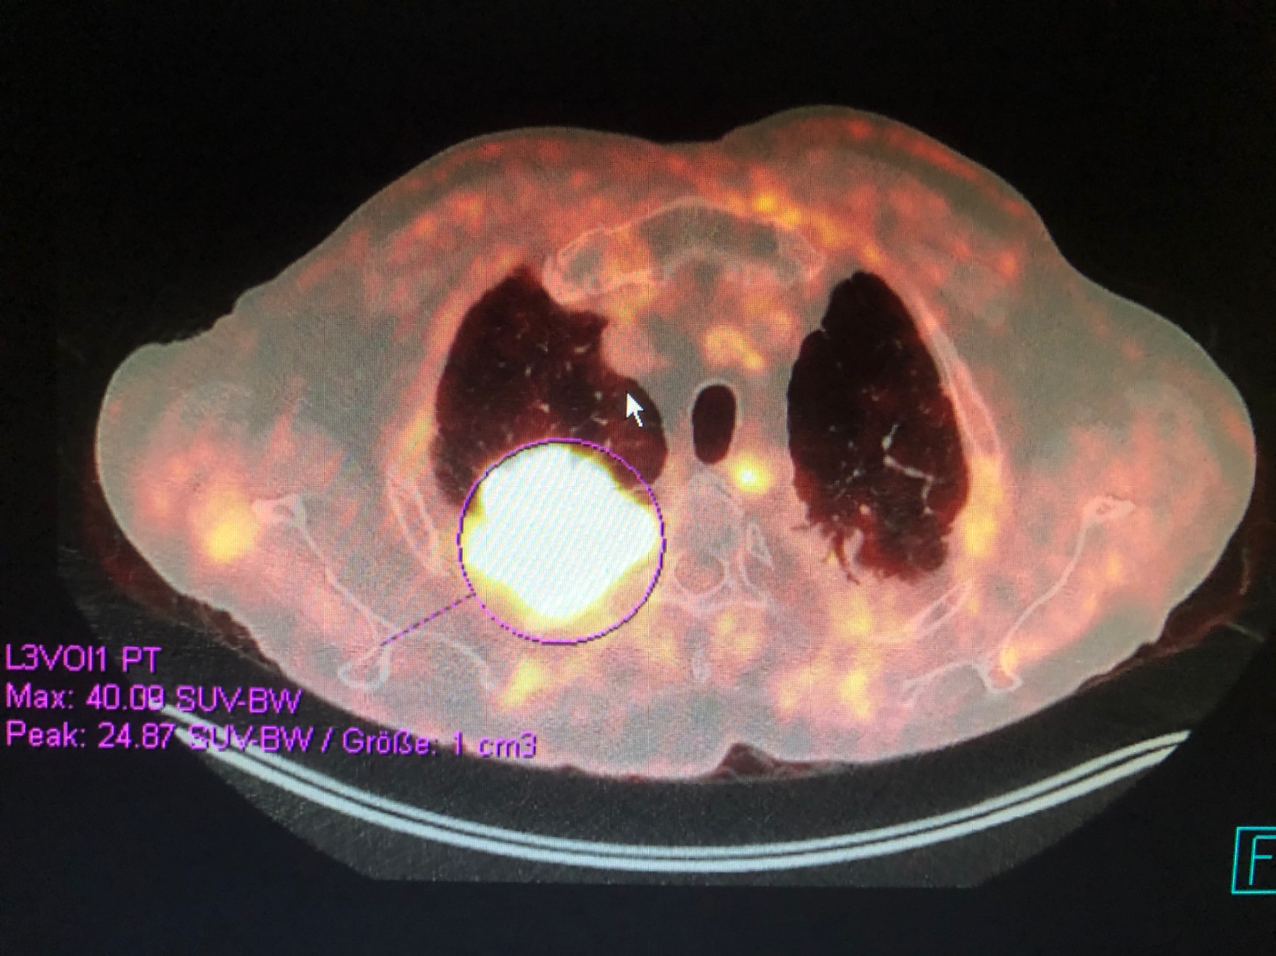

Мета были в лу или легкие и кости?

Нет (ПЭТ вчера)

вот еще ПЭТ